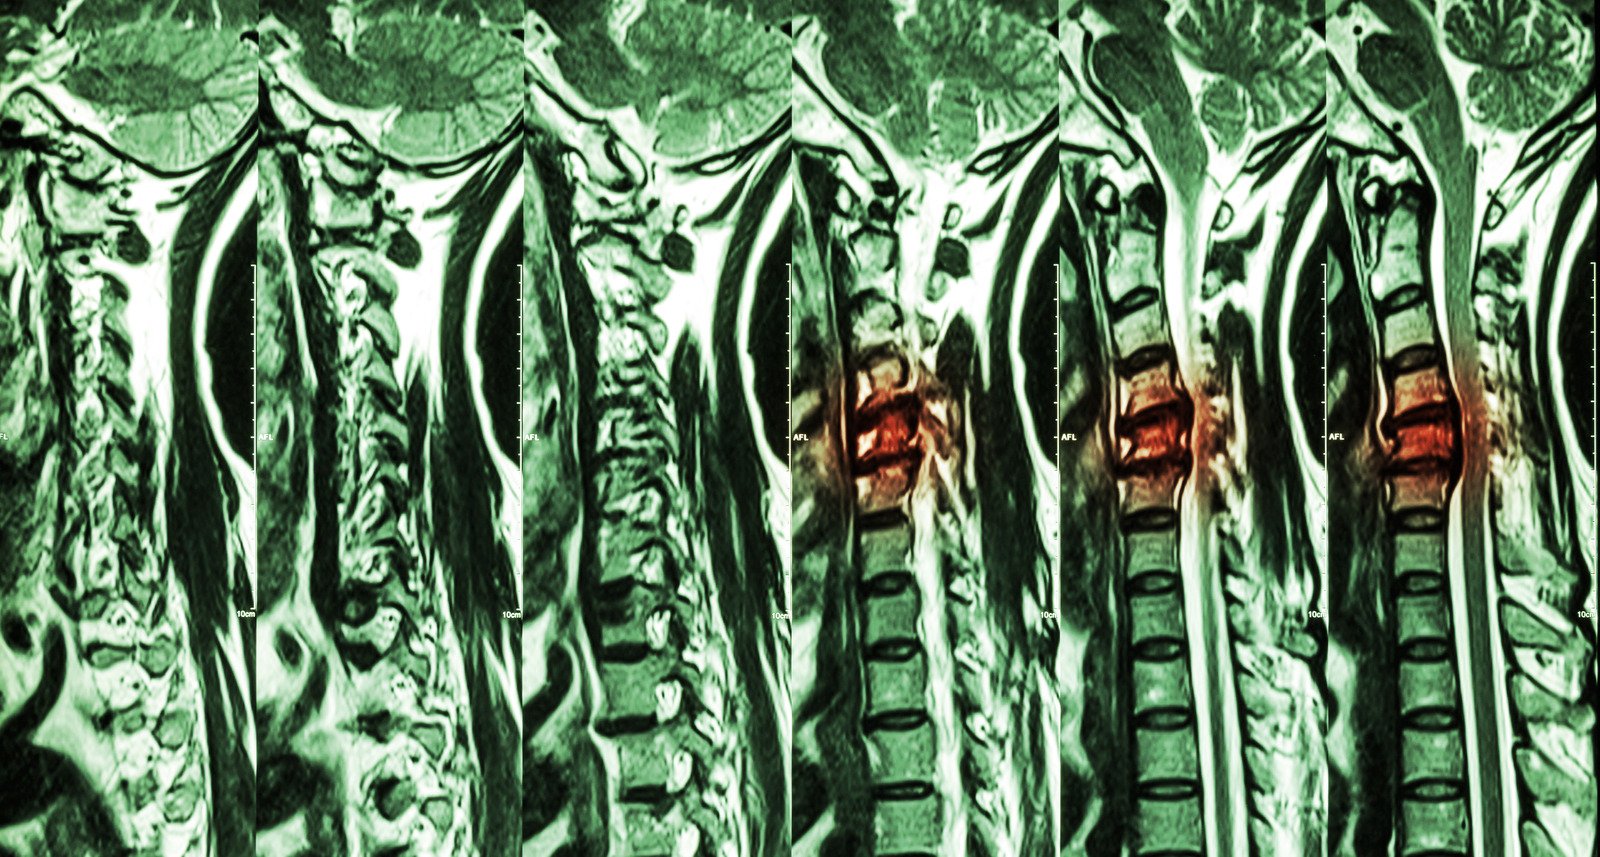

영상 검사

MRI: 신경 압박 여부와 디스크 상태를 명확히 확인합니다.

Q10. 경추 디스크 진단을 위해 어떤 검사가 필요할까요?

MRI 검사는 신경 압박과 디스크 상태를 확인하는 가장 정확한 방법입니다. 필요에 따라 X-ray나 CT 스캔도 시행해 경추의 상태를 종합적으로 평가합니다.